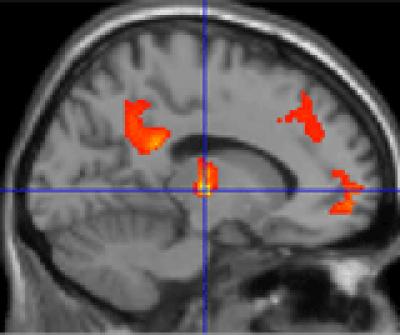

The research, which was published in the journal NeuroImage , uses functional brain imaging to assess how the environment impacts upon our brain functions.

The findings demonstrated that tranquil environmental scenes containing natural features, such as the sea, cause distinct brain areas to become 'connected' with one another whilst man-made environments, such as motorways, disrupt the brain connections.

Using brain scanning that measures brain activity they showed that the natural, tranquil scenes caused different brain areas to become 'connected' with one another – indicating that these brain regions were working in sync. However, the non-tranquil motorway scenes disrupted connections within the brain.